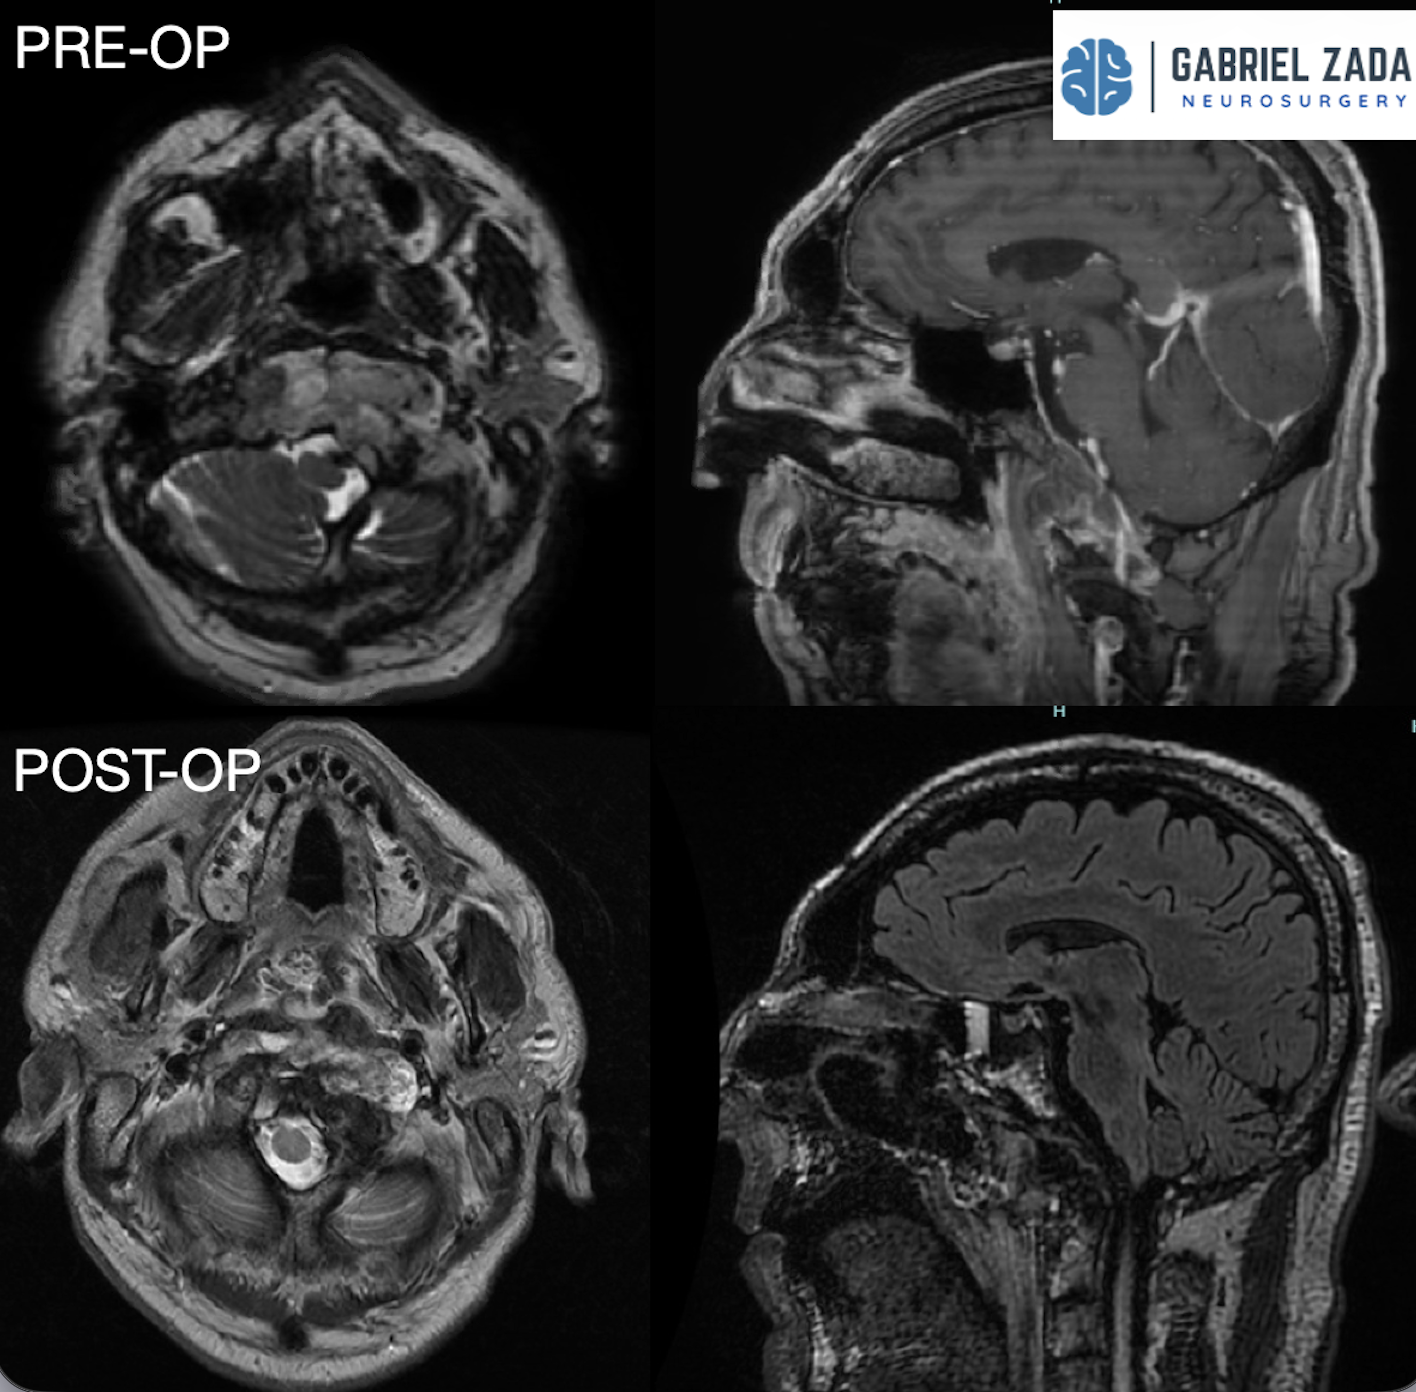

CHONDROSARCOMA surgery

Chordoma surgery treatment

Dr. Zada specializes in endoscopic endonasal approach (EEA) surgery, also known as transsphenoidal surgery, which allows surgeons to reach the pituitary gland through the nasal passages without making external incisions.